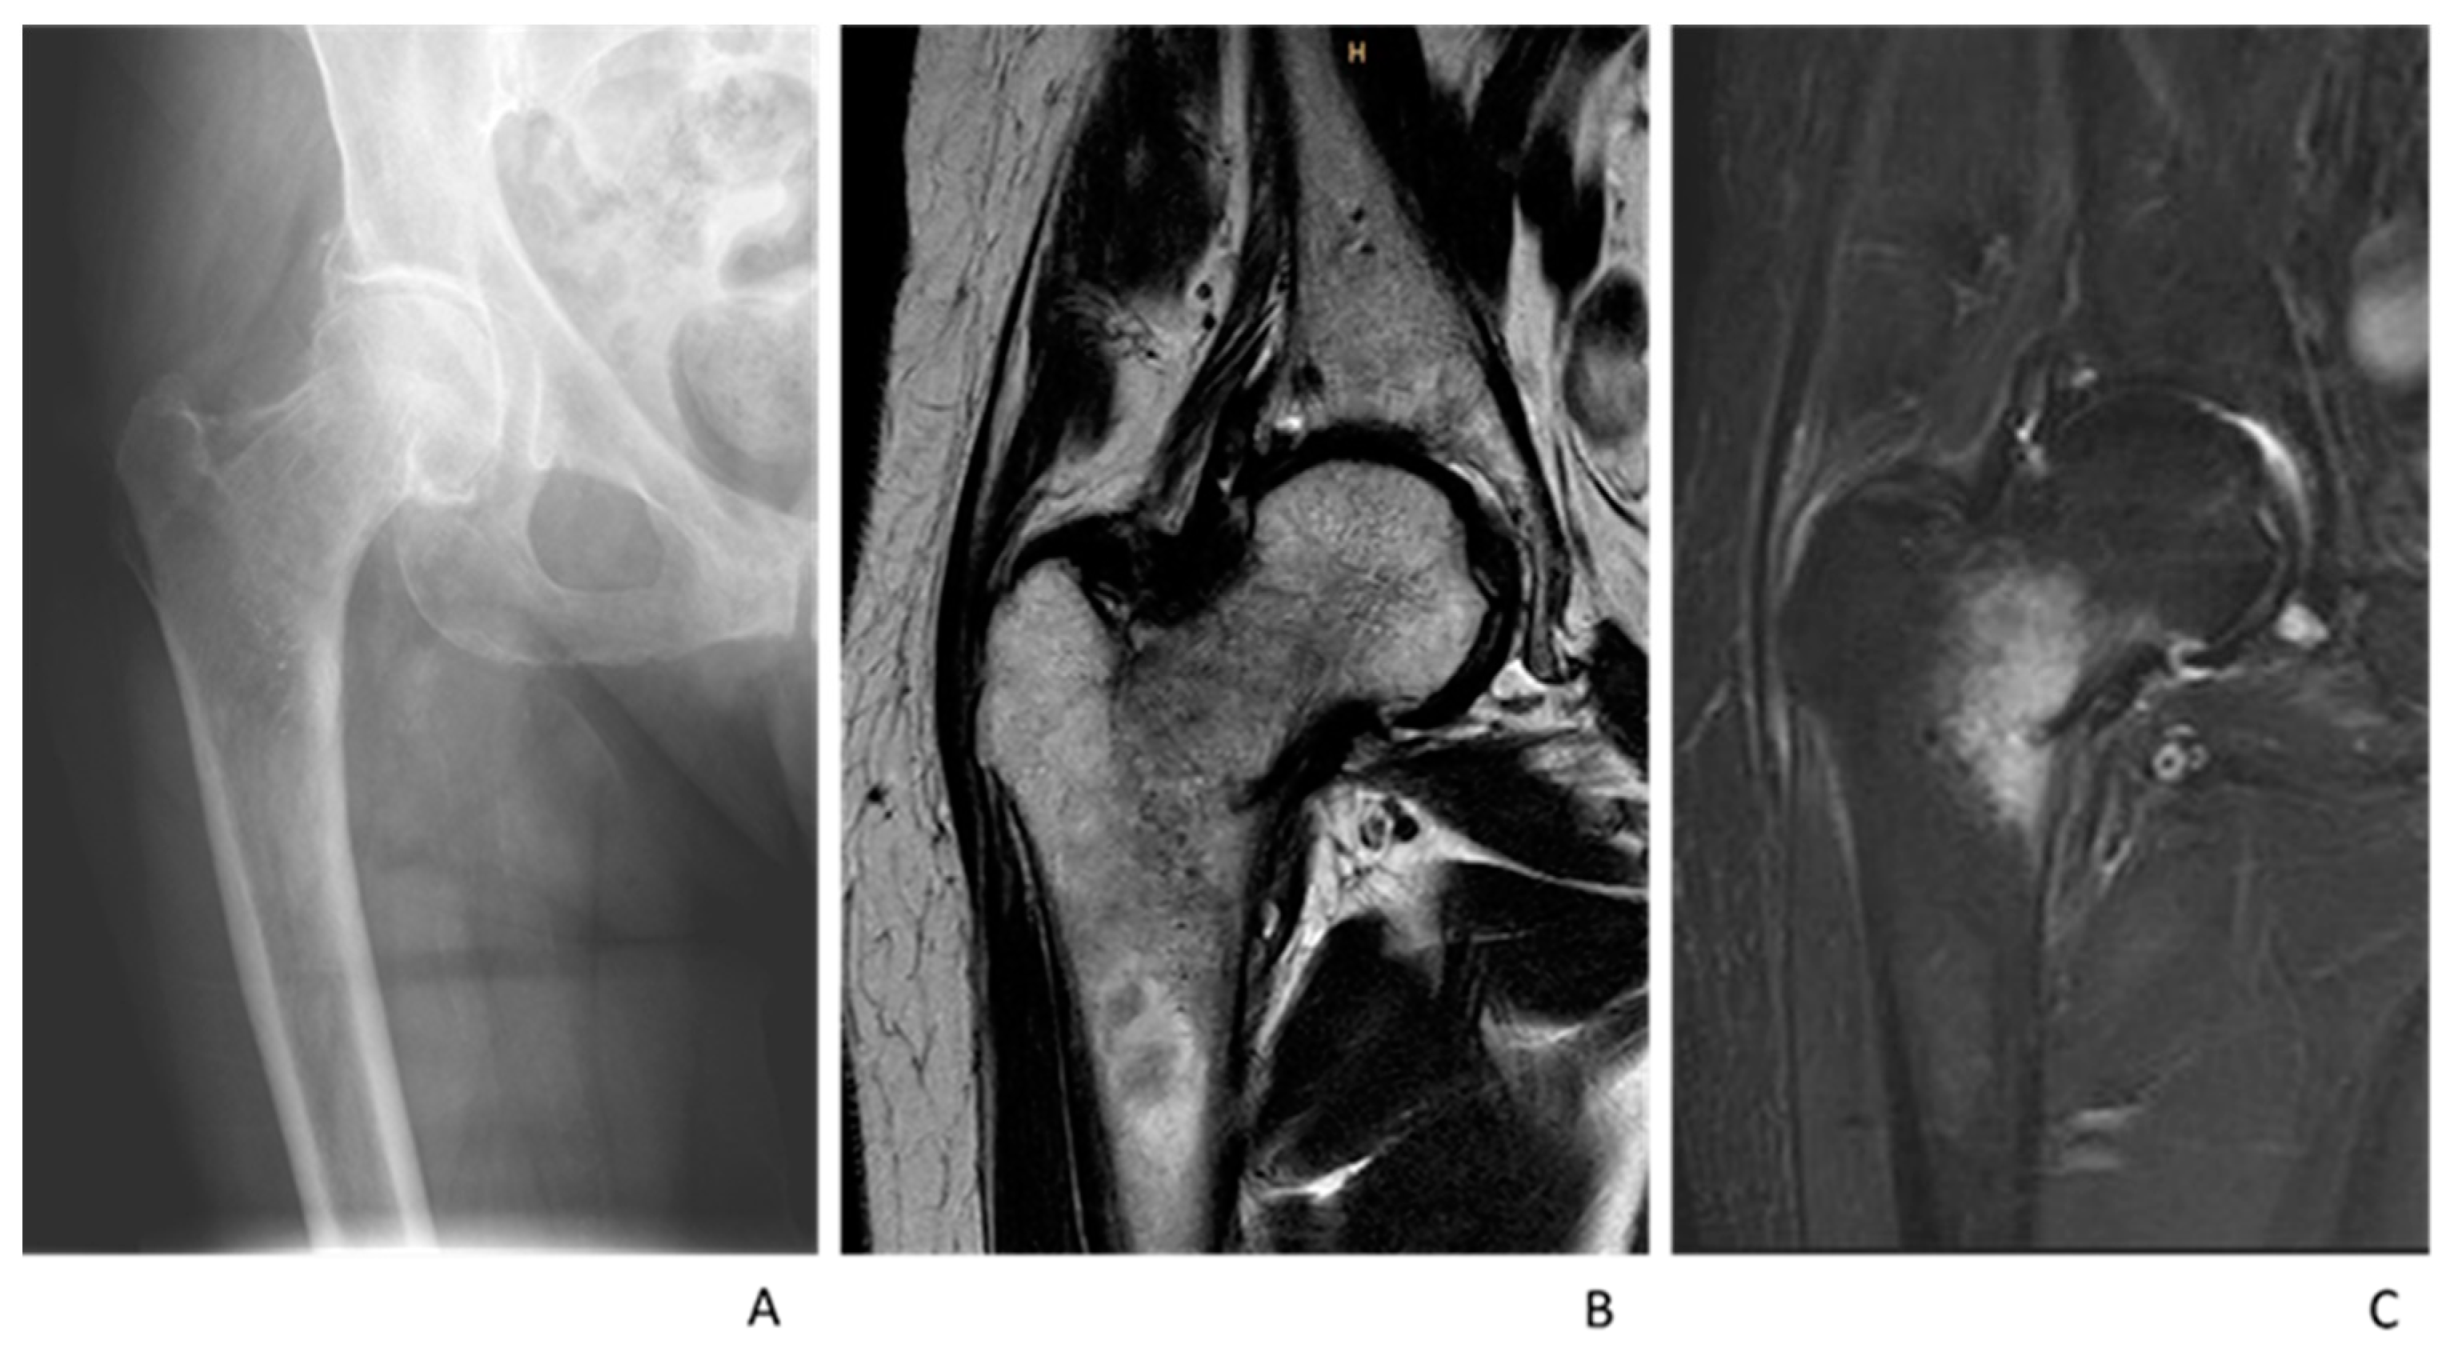

2.3. MRI